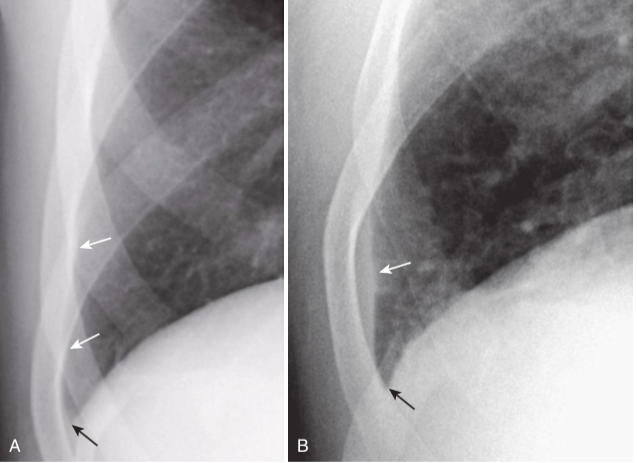

Normal versus laminar pleural effusion.

A, A normal patient in whom the normally aerated lung extends to the inner margin of each of the ribs (white arrows). The costophrenic sulcus is sharp (black arrow). B, There is a thin band of increased density that extends superiorly from the lung base (white arrow) but does not appear to cause blunting of the costophrenic angle (black arrow). This is the appearance of a laminar pleural effusion, which is most often associated with either congestive heart failure or lymphangitic spread of malignancy in the lung. This patient was in congestive heart failure.